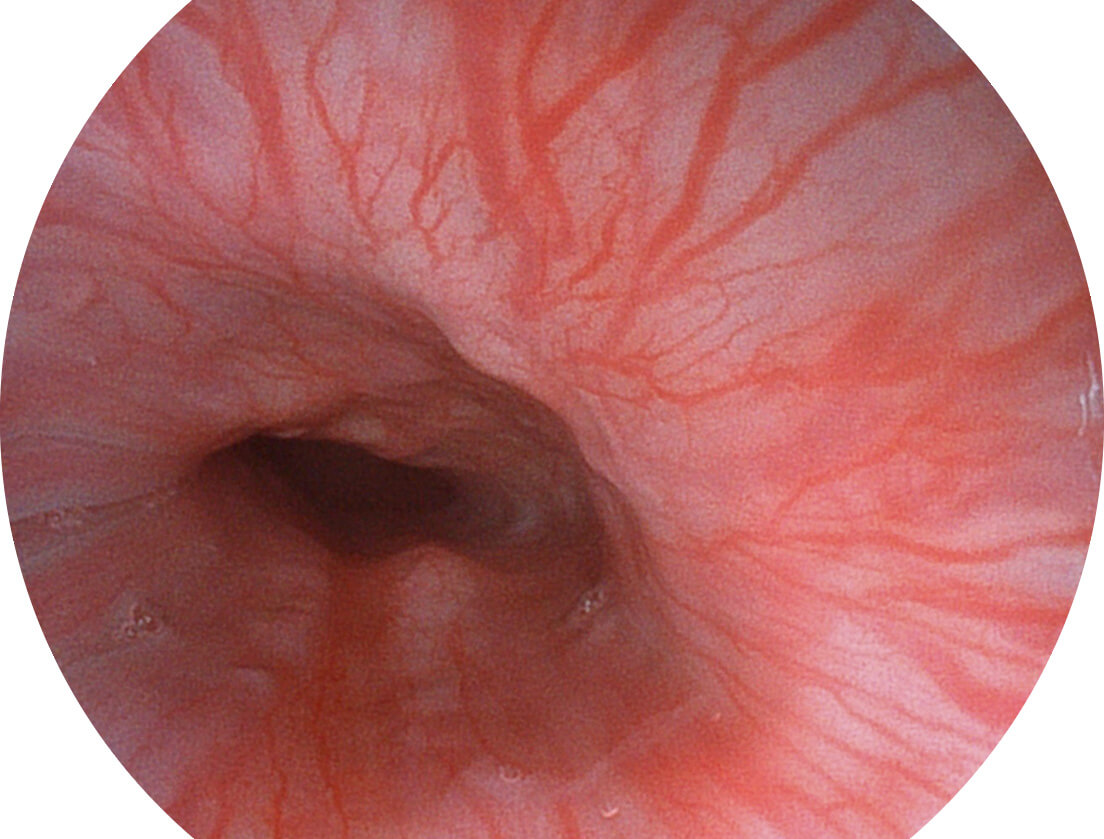

VIST图像